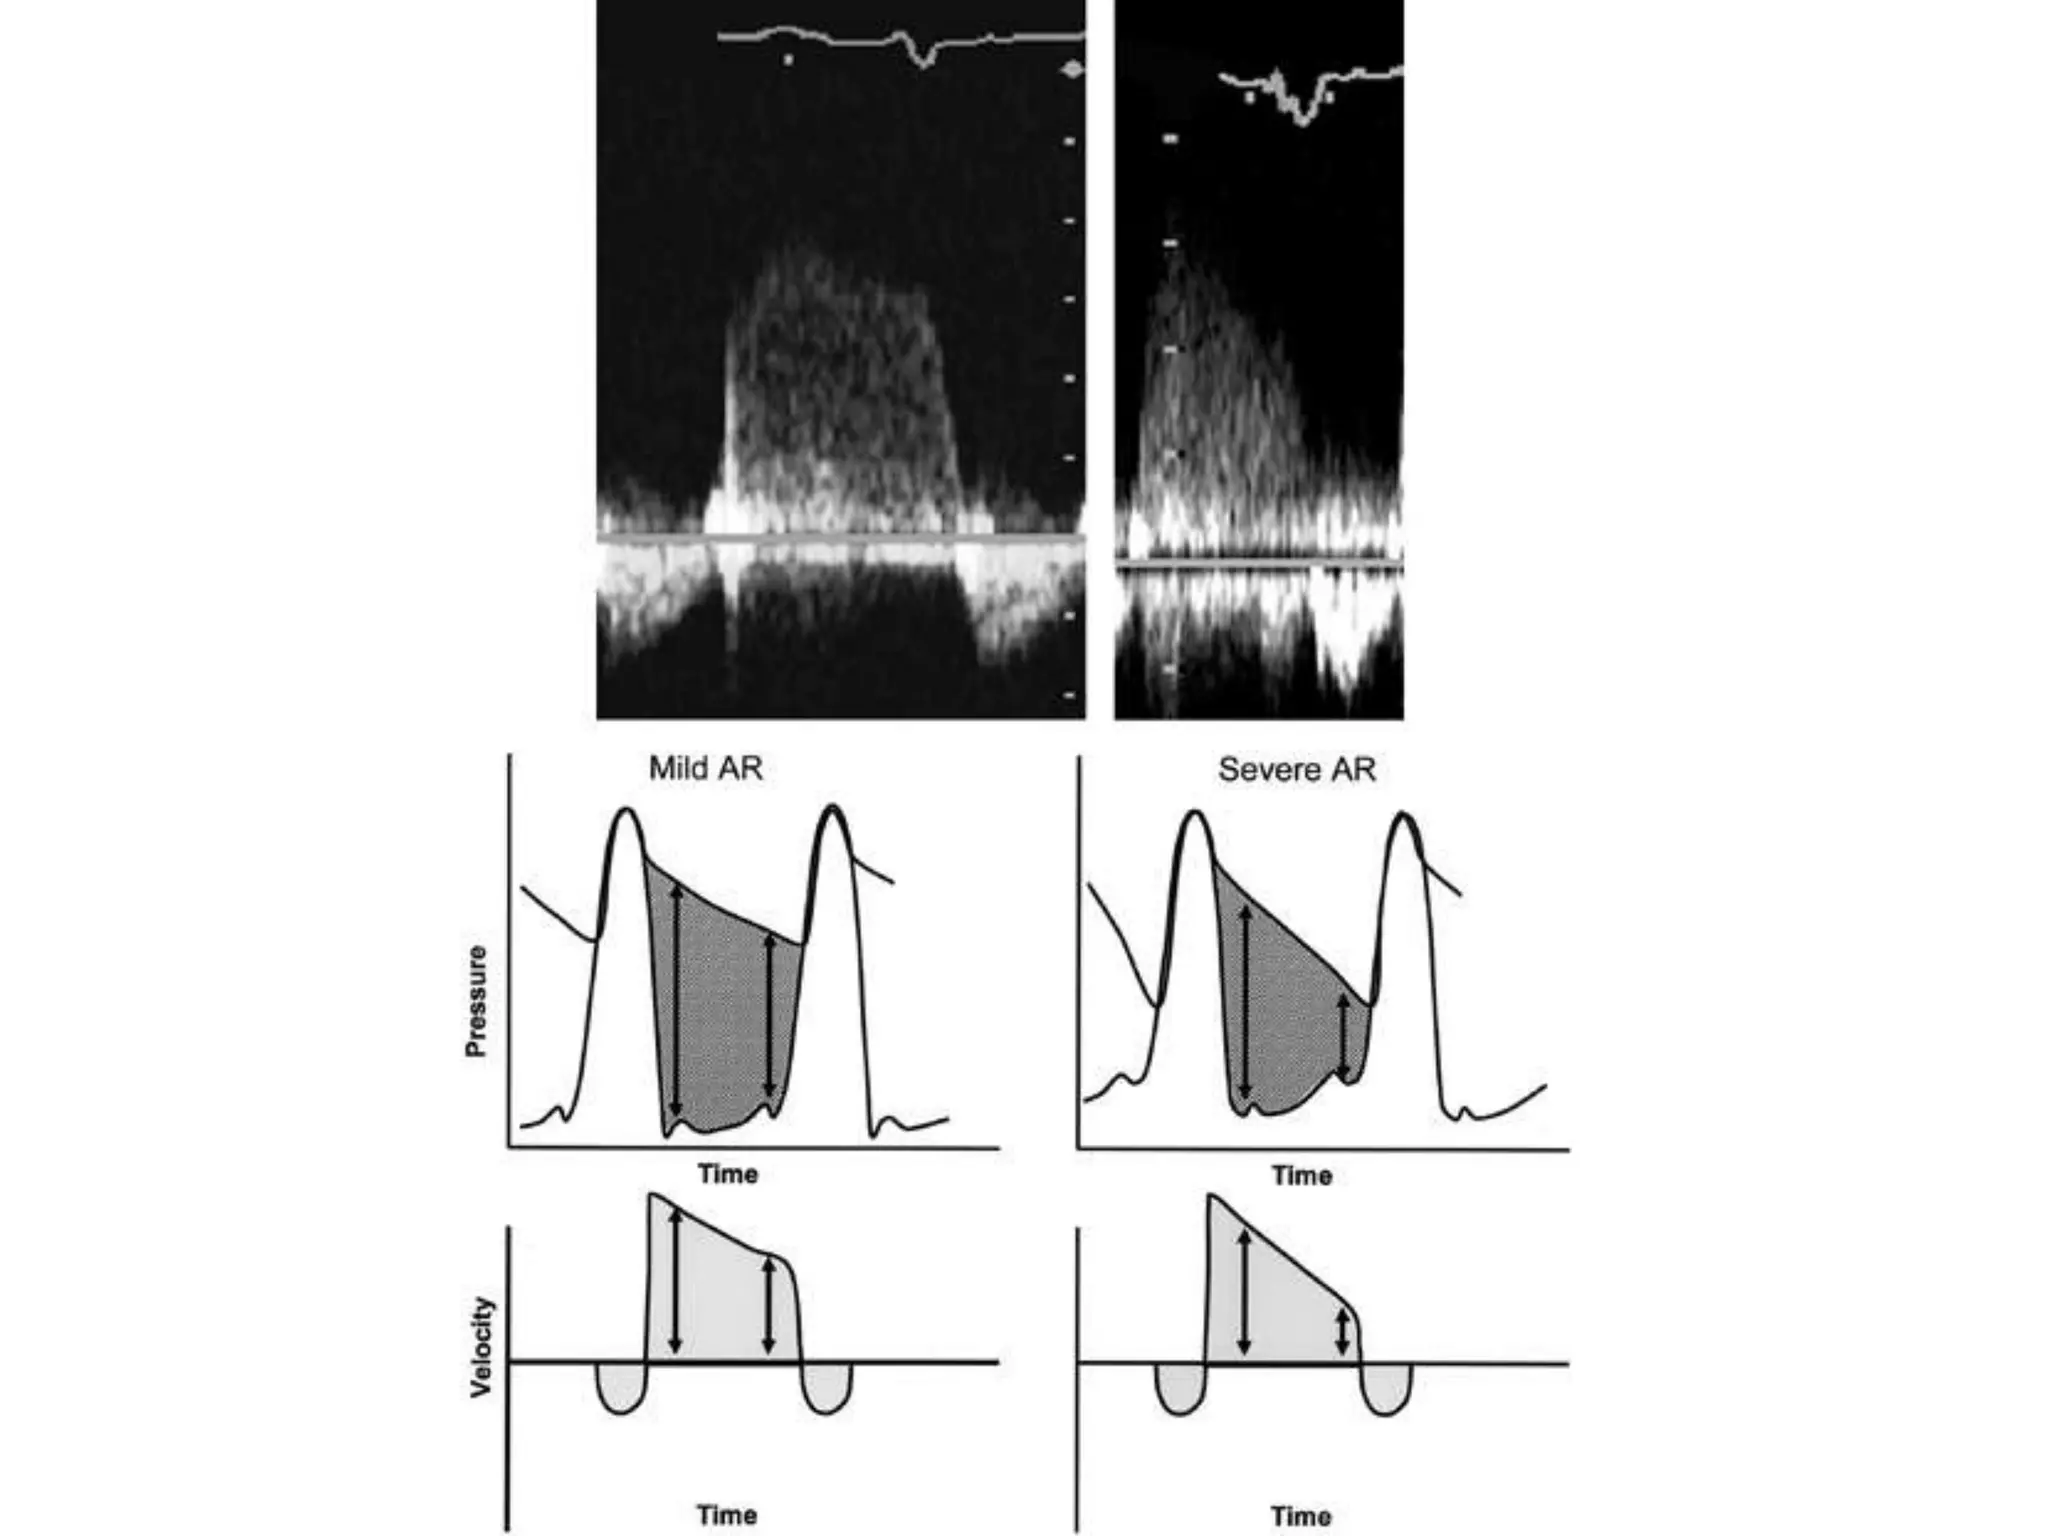

• Regurgitant doppler signal is a function of

pressure gradient between aorta and LV

• Mild AR –small increase in LVEDP-gradual

decline and flat deceleration slope

• Severe AR –LVEDP rises rapidly-rapid decline

• Regurgitant dopplersignal is a function of pressure gradient between aorta and LV • Mild AR –small increase in LVEDP-gradual decline and flat deceleration slope • Severe AR –LVEDP rises rapidly-rapid decline